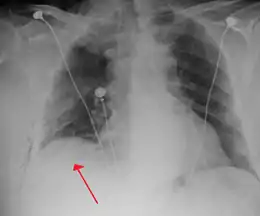

Anteroposterior inspired X-ray, showing subtle left-sided pneumothorax caused by port insertion

Chest X-ray showing a pneumothorax on the right (left in the image), where the absence of lung markings indicates that there is free air inside the chest

Chest X-ray showing the features of pneumothorax on the left side of the person (right in image)

The size of the pneumothorax (i.e. the volume of air in the pleural space) can be determined with a reasonable degree of accuracy by measuring the distance between the chest wall and the lung. This is relevant to treatment, as smaller pneumothoraces may be managed differently. An air rim of 2 cm means that the pneumothorax occupies about 50% of the hemithorax.[14] British professional guidelines have traditionally stated that the measurement should be performed at the level of the hilum (where blood vessels and airways enter the lung) with 2 cm as the cutoff,[14] while American guidelines state that the measurement should be done at the apex (top) of the lung with 3 cm differentiating between a "small" and a "large" pneumothorax.[30] The latter method may overestimate the size of a pneumothorax if it is located mainly at the apex, which is a common occurrence.[14] The various methods correlate poorly but are the best easily available ways of estimating pneumothorax size.[14][18] CT scanning (see below) can provide a more accurate determination of the size of the pneumothorax, but its routine use in this setting is not recommended.[30]

Not all pneumothoraces are uniform; some only form a pocket of air in a particular place in the chest.[14] Small amounts of fluid may be noted on the chest X-ray (hydropneumothorax); this may be blood (hemopneumothorax).[13] In some cases, the only significant abnormality may be the "deep sulcus sign", in which the normally small space between the chest wall and the diaphragm appears enlarged due to the abnormal presence of fluid.[15]